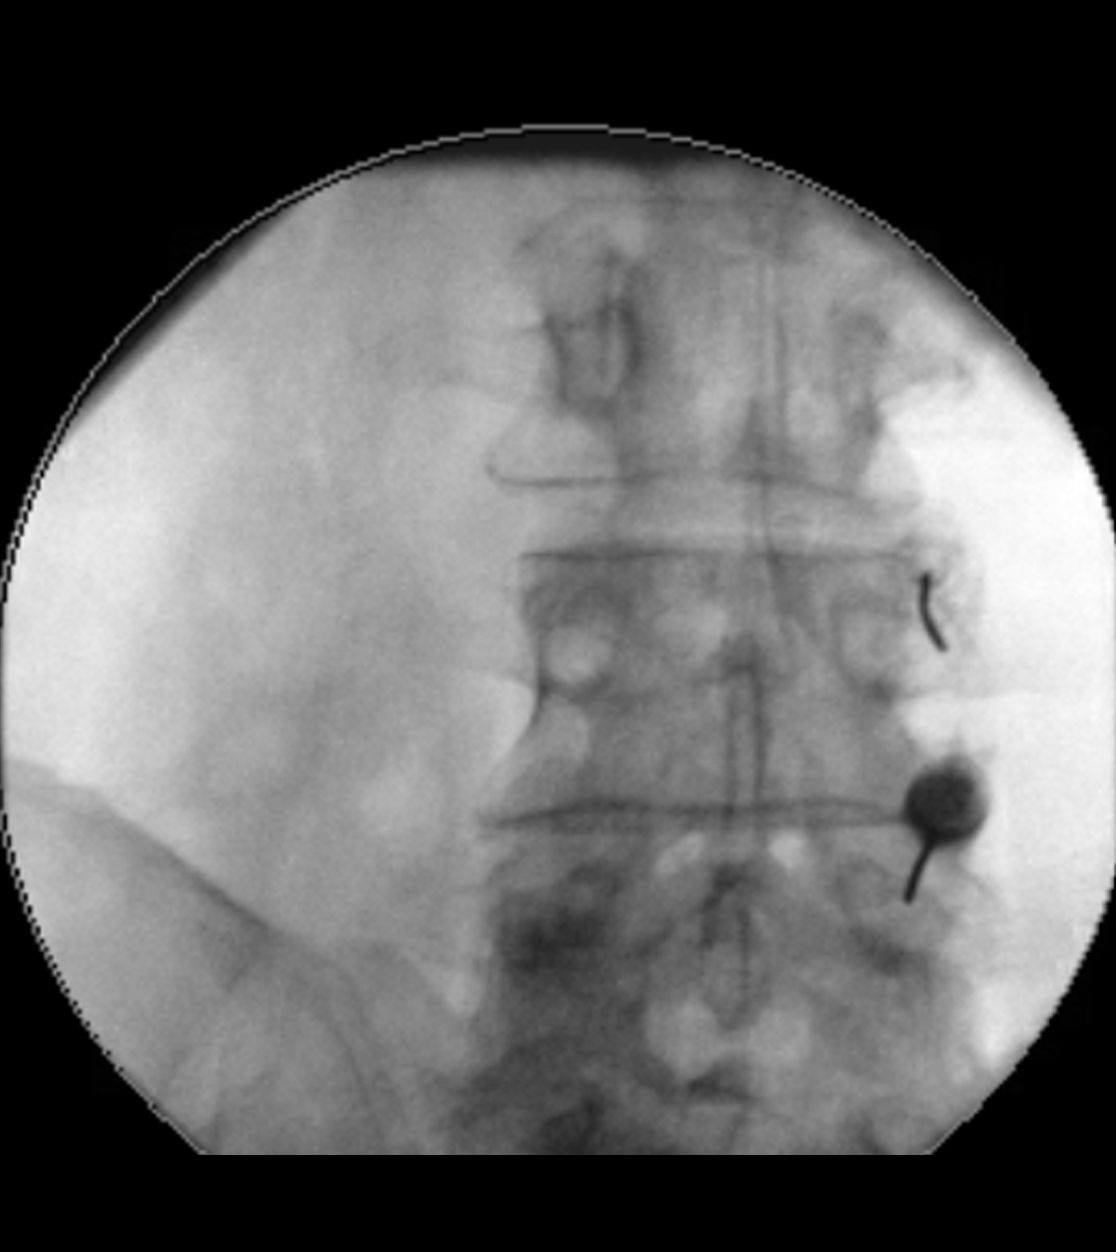

Sollte bei einer Trigeminusneuralgie eine mikrovaskuläre Dekompression nicht infrage kommen, so kann als minimalinvasives Verfahren eine „Verödung“ des Ganglion Gasseri zu einer Schmerzlinderung führen. Hierbei wird unter Röntgenkontrolle eine dünne Nadelelektrode in das Ganglion Gasseri geschoben und mit gezielten Wärmestrahlen eine selektive Vernarbung der Nervenfasern vorgenommen, die für die Schmerzübertragung verantwortlich sind. In einigen Fällen ist im Verlauf bei einer erneuten Zunahme der Beschwerden eine Wiederholung der Prozedur notwendig.

Röntgen-gestützte Infiltrationen stellen eine präzise und schonende Methode zur Behandlung von Rücken- und Gelenkschmerzen dar. Durch den Einsatz von Röntgenbildwandlern wird die genaue Position der Nadel während des Eingriffs sichtbar gemacht, wodurch eine präzise und zielgerichtete Behandlung möglich ist. Zielgebiete der Infiltration sind hierbei die sog. Facettengelenke oder das Ileosakralgelenk (ISG). Wenn die infiltrative Methode nicht ausreicht bzw. die Schmerzlinderung nur kurz anhält, setzen wir auch Facettenthermokoagulationen ein, bei denen durch gezielte Wärmeanwendungen an den betroffenen Nerven die Schmerzübertragung blockiert wird.

Infiltration von Facettengelenken

Infiltration eines Ileosakralgelenks